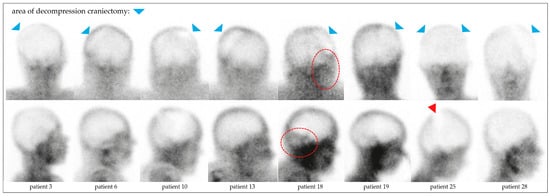

4.3. BPS in Hemicraniectomy